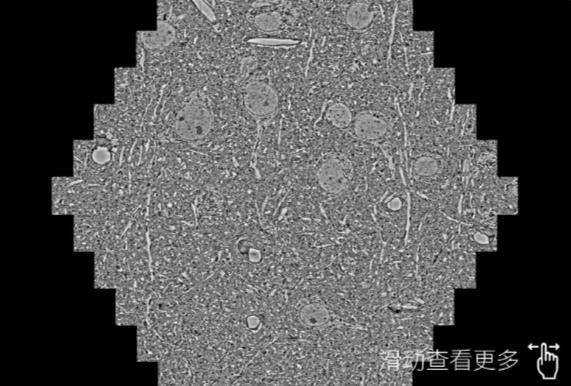

鼠脑切片。左图使用荣昌蔡司荣昌扫描电镜MultiSEM706对165μmx143pm面积区域成像,耗时仅需1.5秒。右图为鼠脑切片中30μm区域放大效果。样品由芝加哥大学B.Kasthuri提供。